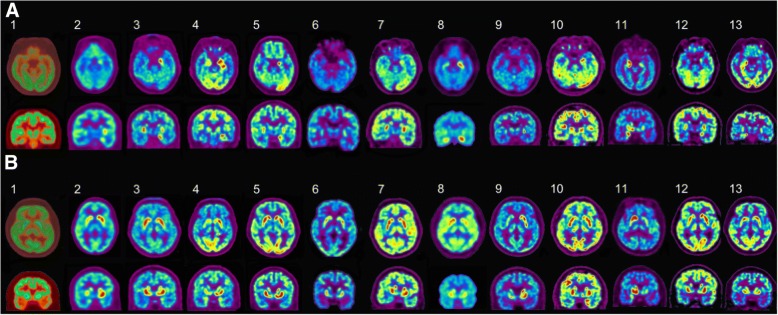

The median time duration from symptom onset to the FDG-PET image was 37 days [IQR 21–42 days]. The patients with LGI1-antibody encephalitis showed asymmetric FDG uptake that was frequently located in the hippocampus (11/13, 84.6%) and the basal ganglia (7/13, 53.9%, Table 1, Fig. 1). In the hippocampus, nine of 11 (81.8%) showed uptake of FDG on the left hippocampus and two (2/11, 18.2%) on the right hippocampus. Overall, ten (90.9%) of the 11 asymmetric hippocampus hot uptake were contralateral to patient handedness (Fig. 1; P = 0.035). In the basal ganglia, among the seven patients (7/13, 53.9%) who had asymmetry, five (71.4%) showed increased FDG uptake on the side contralateral to their handedness (Fig. 1), although this did not reach statistical significance (P = 0.647). The summarized laterality results of the subjects are available in Additional file 1: Figure S1.

Fig. 1.

The pretreatment 18F-FDG-PET images of patients with LGI1-antibody encephalitis. a Axial (upper row) and coronal views (lower row) of the hippocampus: out of the 13 patients, nine (2, 3, 4, 5, 6, 7, 8, 10, and 12) had increased FDG uptake on the left side, two (11, 13) had on the right side, and two (1, 9) had no laterality. b Axial (upper row) and coronal views (lower row) of the basal ganglia: seven (1, 2, 4, 8, 9, 11, and 12) had asymmetric FDG uptake in the basal ganglia. Among them, four (2, 4, 9, and 12) had increase uptake on the left side, and three (1, 8, and 11) on the right side. All patients were right-handed except one (11), who was left-handed. R = right, L = left, 18F-FDG-PET = 18F-fluoro-2-deoxy-d-glucose positron emission tomography, LGI1 = leucine-rich glioma-inactivated 1